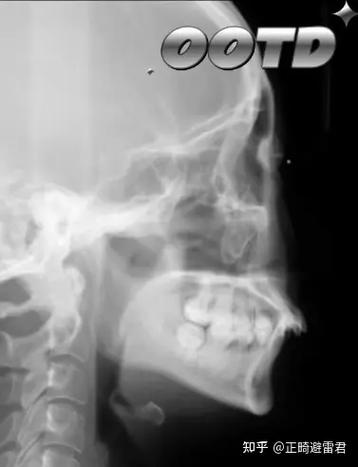

- 影像学检查:拍摄全景片、头颅侧位片(用于分析骨骼与牙齿关系),必要时进行CBCT扫描;

患者主诉“上前牙突出,影响美观”,检查显示为安氏Ⅱ类错颌,上颌前突,下颌后缩,伴有轻度拥挤,医生采用“功能矫治器+固定托槽”联合治疗:先佩戴 Herbst 矫治器引导下颌前移,改善骨骼关系,再通过固定托槽精细调整牙齿排列,治疗时间18个月,矫正后,牙齿排列整齐,侧貌突度明显改善,面部比例协调。